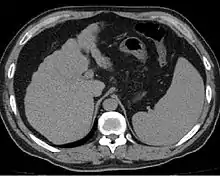

Other scans include CT of the abdomen and MRI.[34] A CT scan is non-invasive and may be helpful in the diagnosis.[34] Compared to the ultrasound, CT scans tend to be more expensive. MRI provides excellent evaluation; however, is a high expense.[34]